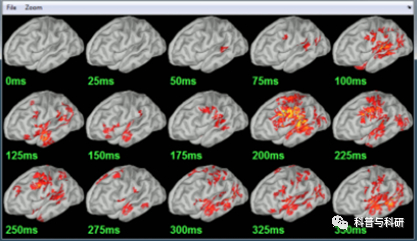

l溯源分析概述 l头模型的构建及正向传递矩阵的计算 l溯源的常用算法(MNE, LORETA, Beamformer)及具体代码详解 l溯源分析中的注意事项 |